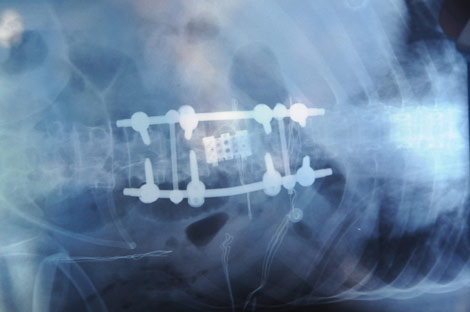

Doğu Karadeniz Bölgesi’nde ilk kez gerçekleştirilen ameliyata 3 ayrı branşta 6 doktor katıldı. Ameliyat 11 saat sürdü. Beyin Cerrahi Uzmanı Doç Dr. Onur Yaman kontrolündeki ameliyatta kırılan omuriliğe 8 çivili yapay omurilik nakli yapıldı.

Beyin Cerrahi Uzmanı Doç Dr. Onur Yaman yaptığı açıklamada, “Ameliyatımız iki aşamalı oldu. İlk aşamada hastanın kırık bel omurgasını çıkararak bunun yerini tutacak açılabilir kafes dediğimiz bir parça koyduk. Ardından hastayı yüzükoyun çevirerek yerleştirdiğimiz parçayı 8 vida ile sabitleştirdik. Şuanda hastamızın sağlık durumu oldukça iyi, yarın sabah ayağa kalkmasını bekliyoruz.” dedi.